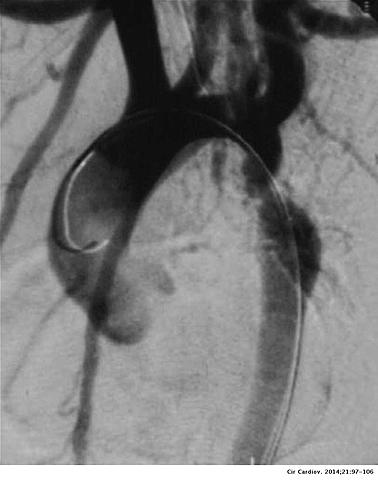

• M. Sones descubrió la coronariografía, lo que permitía ver la anatomía de las arterias coronarias

M. Sones descubrió la coronariografía, lo que permitía ver la anatomía de las arterias coronarias